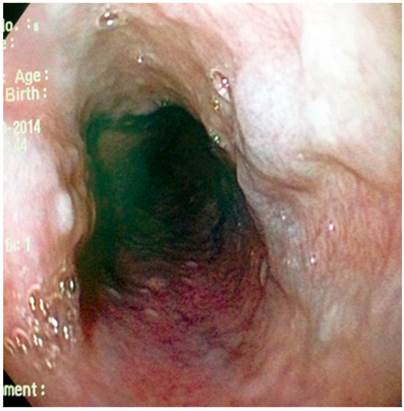

Paciente AMDA: mujer de 73 años con diagnóstico clínico de RGE, con antecedente de EPOC por exposición al humo de leña, uso permanente de inhaladores y oxígeno suplementario en casa. En el momento del examen físico se presenta con obesidad, cianosis de piel y mucosas y abotagamiento (Figura 2). En la EGD, se encontraron várices en los 6 primeros centímetros del esófago (Figura 3) con ausencia distal de estas (Figura 4), sin estigmas de sangrado o de riesgo y gastritis crónica superficial.